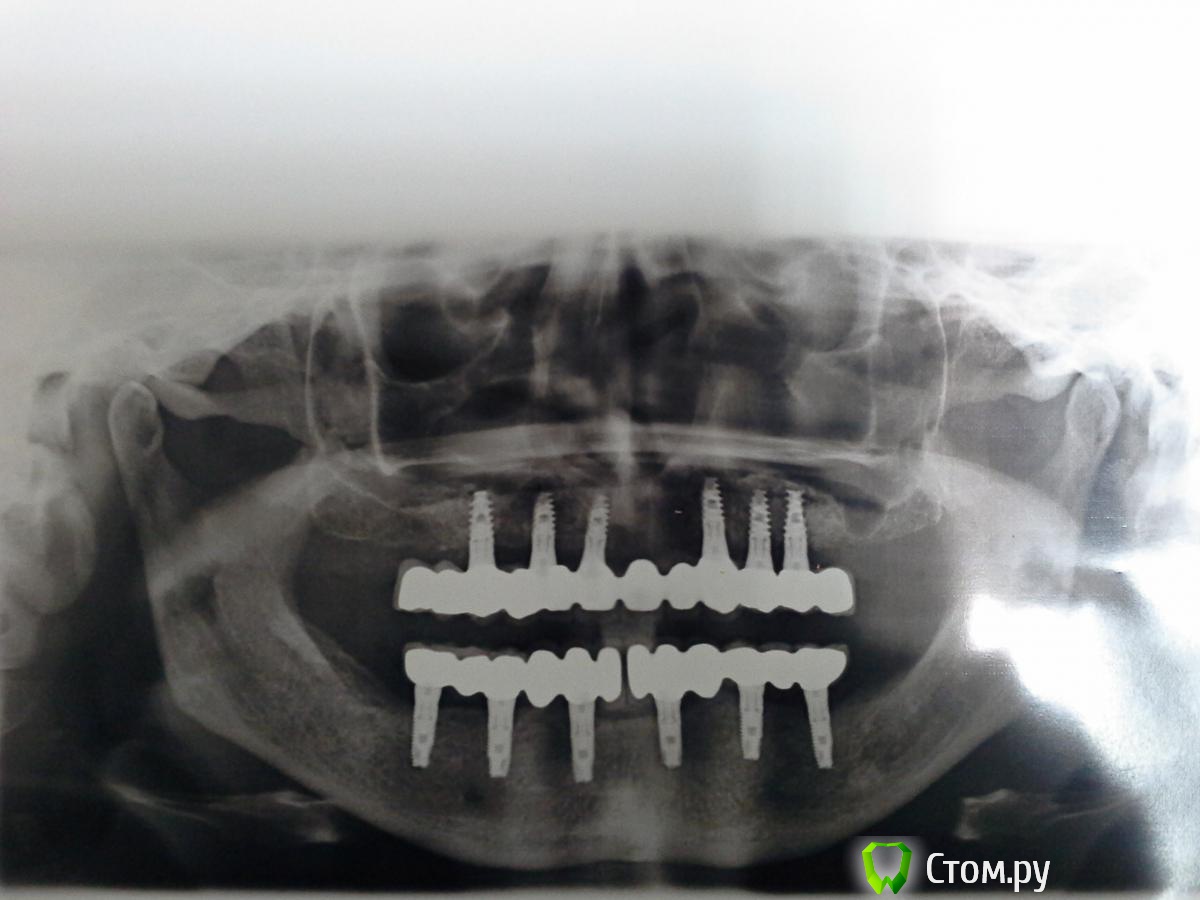

Magomed Опубликовано 3 сентября, 2014 Поделиться Опубликовано 3 сентября, 2014 (изменено) работу делал год. в.ч.удалил 8 з. низ 6 з. в.ч. каркас фрезеров. низ литьё. Изменено 3 сентября, 2014 пользователем Magomed Ссылка на комментарий

anvladd Опубликовано 4 сентября, 2014 Поделиться Опубликовано 4 сентября, 2014 смущают консоли на верху. Ссылка на комментарий

Bier Опубликовано 4 сентября, 2014 Поделиться Опубликовано 4 сентября, 2014 смущают консоли на верху.чем? есть же формула, уверен они вписываются в нее. Ссылка на комментарий

ILGAMSA Опубликовано 4 сентября, 2014 Поделиться Опубликовано 4 сентября, 2014 смущают консоли на верху.По ITI если протяженность протяженность конструкции не менее 30мм, то длина консоли может достигать... внимание(!)... 15мм! 1 Ссылка на комментарий

Bier Опубликовано 4 сентября, 2014 Поделиться Опубликовано 4 сентября, 2014 влияет не количество опор, а передне-задний размер. между передним и задним имплантатом. 1 Ссылка на комментарий

Magomed Опубликовано 5 сентября, 2014 Автор Поделиться Опубликовано 5 сентября, 2014 Здравствуйте, сколько прошло от момента имплантации верх и них и от протезирования верх и низ?низ 8 мес. верх 2 нед. протезирования Ссылка на комментарий

Magomed Опубликовано 5 сентября, 2014 Автор Поделиться Опубликовано 5 сентября, 2014 (изменено) и мне каж.консоль здесь не навредит. Изменено 5 сентября, 2014 пользователем Magomed Ссылка на комментарий